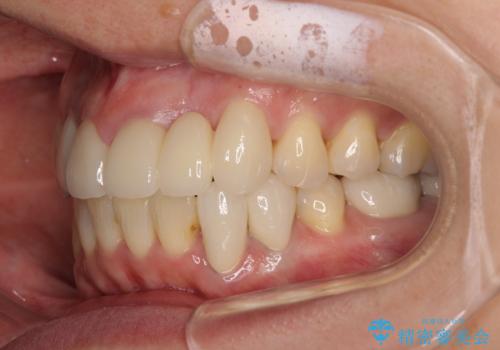

前歯の横幅が大きいことも気になっていたので、矯正治療で前歯5本の幅をコントロールしながら移動させ、治療開始前より一回りサイズの小さいセラミッククラウンを装着することができました。